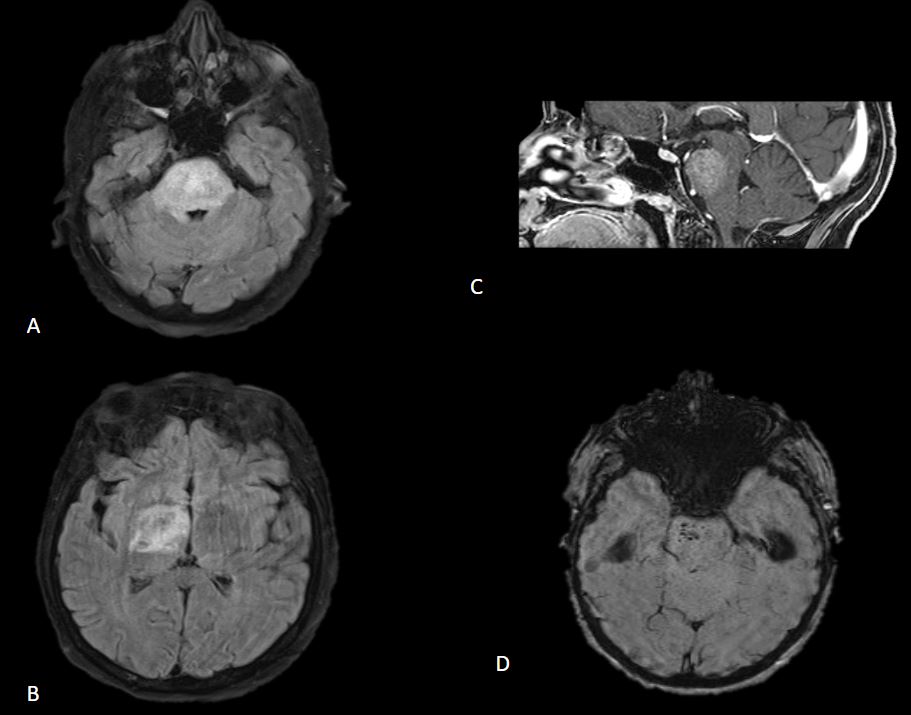

RM cerebral: Extensa lesión hiperintensa de aspecto tumefacto en secuencia T2-Flair que afecta a la totalidad de la protuberancia y se extiende a tálamo derecho (A y B). La lesión presenta tenue realce difuso en secuencia T1 con gadolinio (C). Se observan focos de hemorragia puntiforme protuberancial asociados en secuencia de susceptibidad magnética (D).

El diagnóstico radiológico se realiza mediante RM, en la que se observan extensas lesiones tumefactas de aspecto desmielinizante hiperintensas en T2, con menor edema del esperado para el tamaño de las lesiones, realce parcheado en secuencias T1 con gadolinio (la ausencia de realce no excluye el diagnóstico) y focos de hemorragia puntiforme hipointensos en secuencias de susceptibilidad magnética.